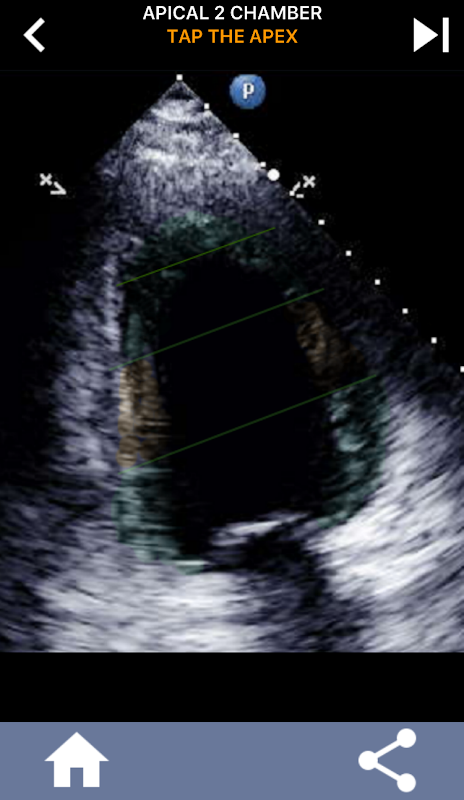

Cette application contient toutes les vues d'écho montrant le myocarde segmenté en AHA et vous demandera de taper le bon segment. Personnellement, je trouve que les interrogations répétitives me conviennent mieux lorsque j'ai besoin d'apprendre / de mémoriser rapidement un sujet. Si vous êtes étudiant en échographie et que vous étudiez écho / TTE, je pense que ce serait un excellent complément à vos études.